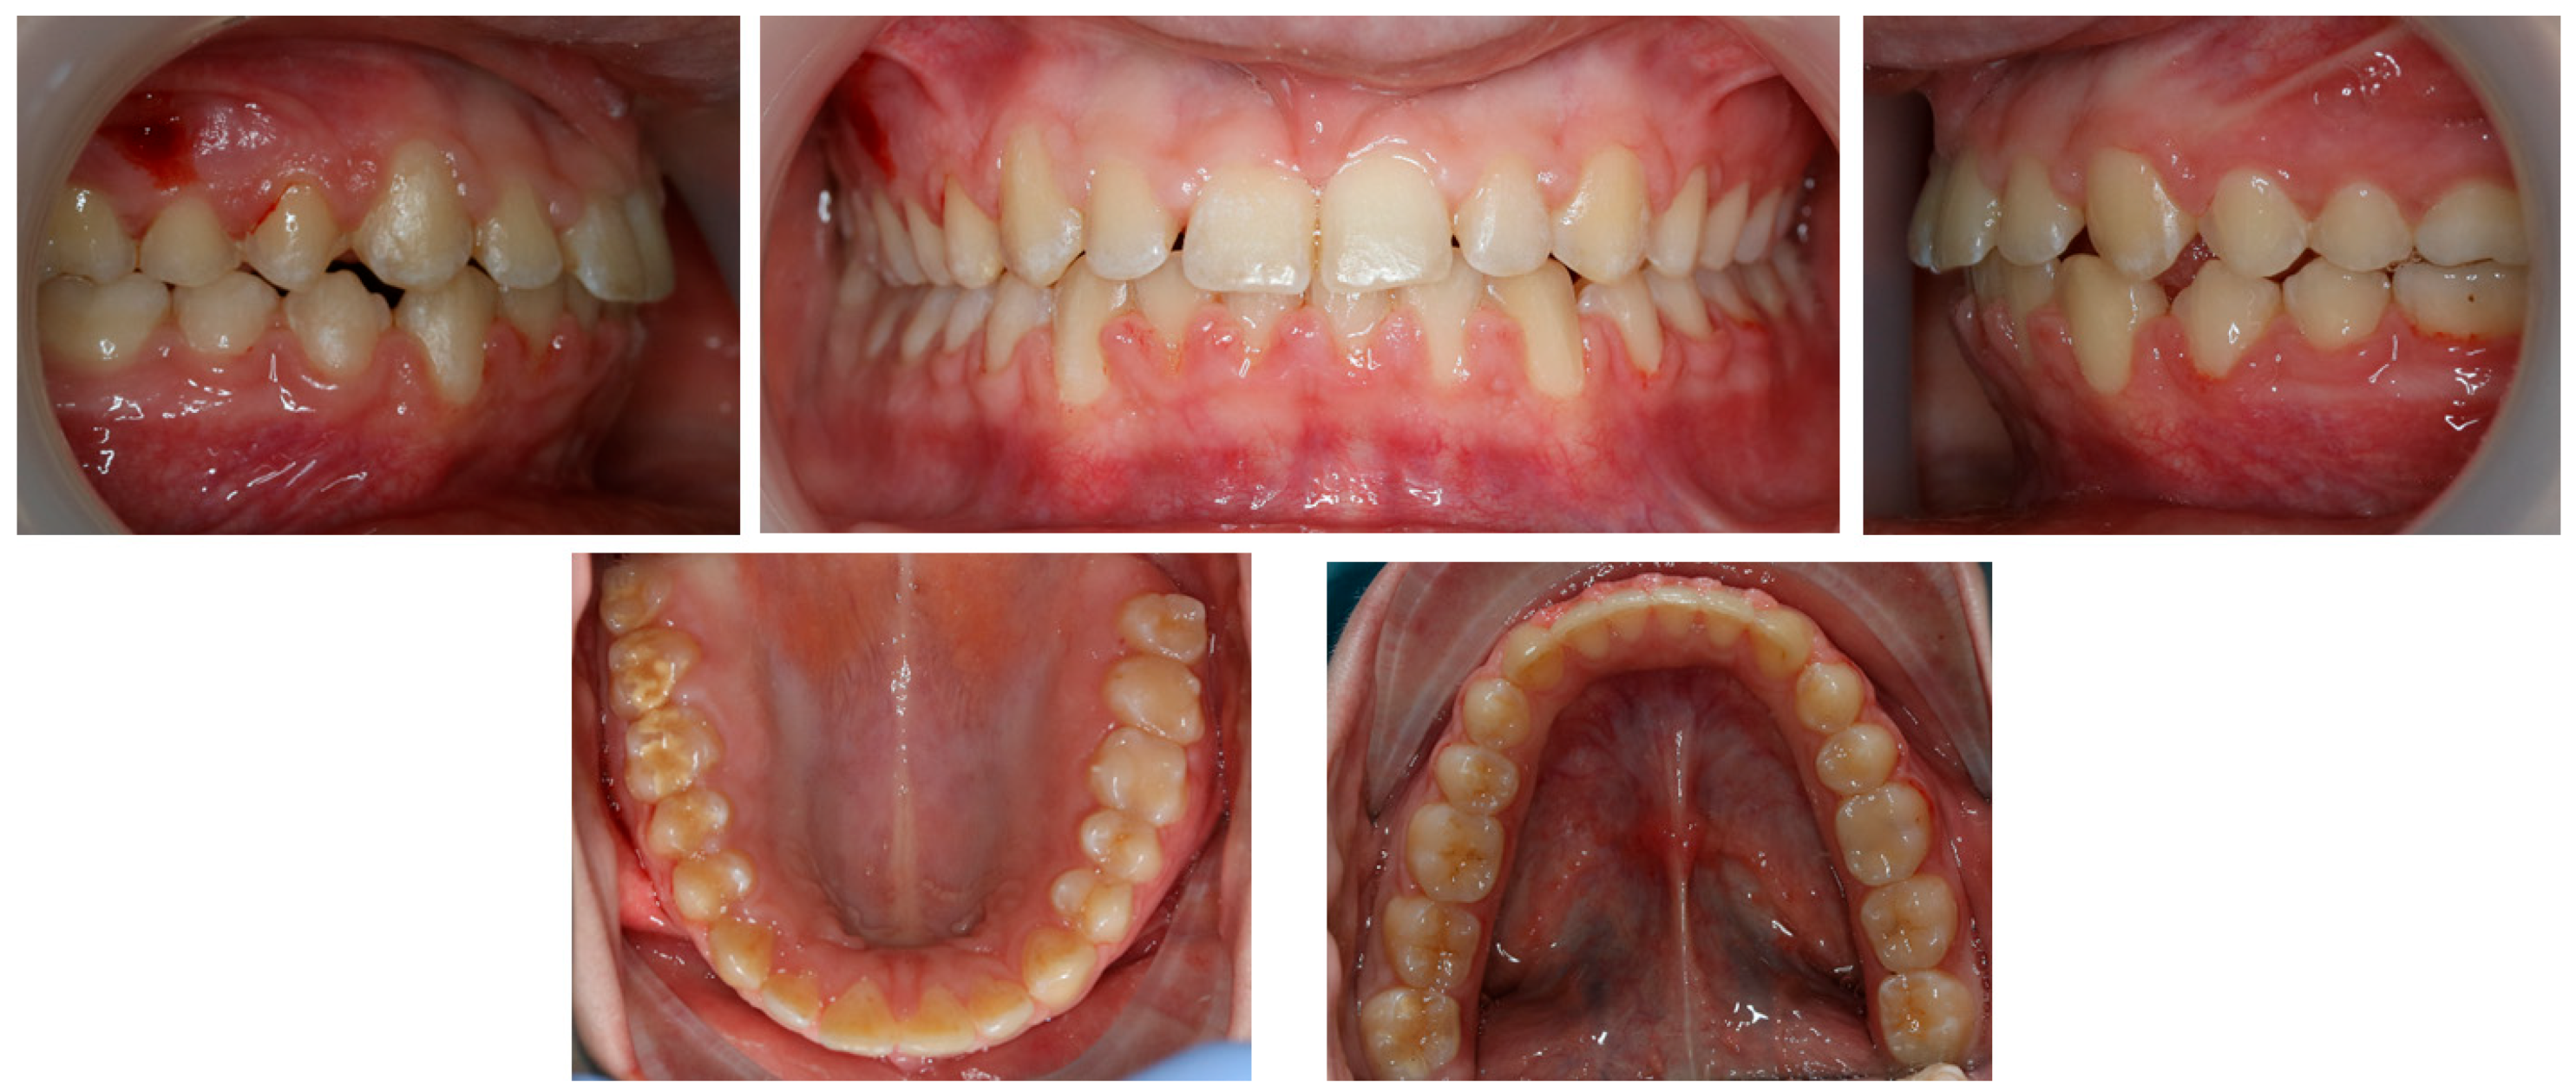

2.1. Diagnosis and Aetiology

2.2. Treatment Objectives

2.3. Treatment Progress